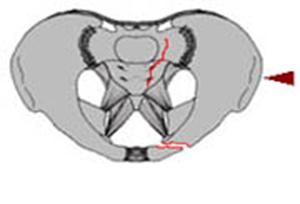

Compresie laterala

Fracturi pelviene multiple Fracturi pelviene multiple

Compresie bilaterala Compresie bilateralaAspect CT

Fracturi pelviene multiple Fracturi bilaterale de ramuri pubiene

Compresie bilaterala Aspect CT Disjunctie sacro-iliaca stanga Compresie antero-posterioara